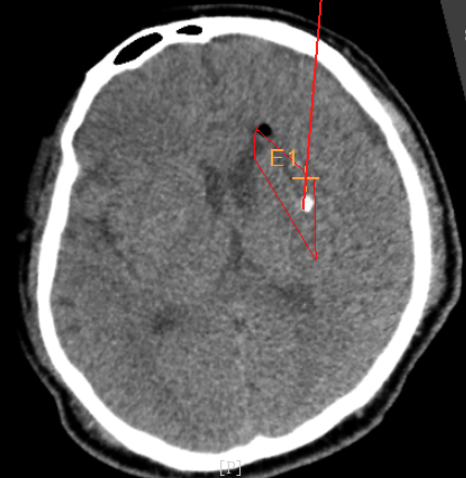

術后CT:血腫腔消失